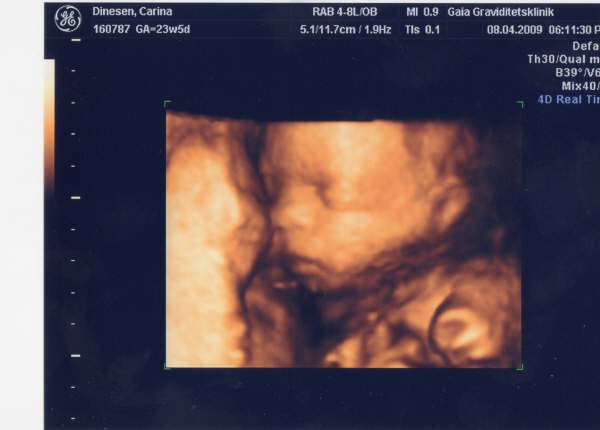

Jeg var til 3D scanning .. Og det var en helt fantastisk oplevelse .. Prøver og se om jeg kan finde et billede ..

Jeg var i Hobro .. Og hun er så kanon sød ..

Ej tak! Mega fedt at se et foto fra den klinik vi skal hen til! Nice nice nice Fik du også DVD med hjem?

Jeps det gjorde jeg .. Og en masse billeder .. Og hvis man har lyst kan man købe et USB stik på 2 gb med ekstra billeder på .. Det skal vi denne gang ..